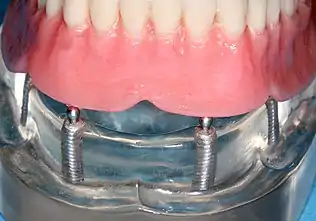

Implant-supported overdenture

A removable implant supported denture (also an implant supported overdenture[17]: 31 ) is a removable prosthesis which replaces teeth, using implants to improve support, retention and stability. They are most commonly complete dentures (as opposed to partial), used to restore edentulous dental arches.[11] The dental prosthesis can be disconnected from the implant abutments with finger pressure by the wearer. To enable this, the abutment is shaped as a small connector (a button, ball, bar or magnet) which can be connected to analogous adapters in the underside of the dental prosthesis.

Prosthetic procedures for removable dentures

When a removable denture is worn, retainers to hold the denture in place can be either custom made or "off-the-shelf" (stock) abutments. When custom retainers are used, four or more implant fixtures are placed and an impression of the implants is taken and a dental lab creates a custom metal bar with attachments to hold the denture in place. Significant retention can be created with multiple attachments and the use of semi-precision attachments (such as a small diameter pin that pushes through the denture and into the bar) which allows for little or no movement in the denture, but it remains removable.[17]: 33–34 However, the same four implants angled in such a way to distribute occlusal forces may be able to safely hold a fixed denture in place with comparable costs and number of procedures giving the denture wearer a fixed solution.[54]

Alternatively, stock abutments are used to retain dentures using a male-adapter attached to the implant and a female adapter in the denture. Two common types of adapters are the ball-and-socket style retainer and the button-style adapter. These types of stock abutments allow movement of the denture, but enough retention to improve the quality of life for denture wearers, compared to conventional dentures.[55] Regardless of the type of adapter, the female portion of the adapter that is housed in the denture will require periodic replacement, however the number and adapter type does not seem to affect patient satisfaction with the prosthetic for various removable alternatives.[56]